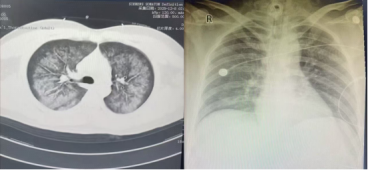

左圖12月8日胸部CT,右圖12月14日床旁胸片

當(dāng)天14時(shí)前,遵醫(yī)附院重癥醫(yī)學(xué)團(tuán)隊(duì)抵達(dá)該院ICU,即刻投入搶救。該30歲男性患者因“咳嗽、咳痰1月余,呼吸急促伴咯血12+小時(shí)”入院。1月前受涼后咳嗽咳痰,自服感冒藥無效;12+小時(shí)前突發(fā)劇烈咳嗽、氣促、鮮紅色咯血及嘔吐咖啡色胃內(nèi)容物,家屬于當(dāng)日凌晨3時(shí)25分送至松桃縣人民醫(yī)院急診科,經(jīng)胸部CT診斷為“肺部感染”,收入重癥醫(yī)學(xué)科。

經(jīng)精準(zhǔn)救治,患者病情逐步好轉(zhuǎn),肺部感染得到控制,于12月13日順利撤機(jī),后續(xù)繼續(xù)氣管切開呼吸機(jī)輔助通氣。隨著炎癥指標(biāo)下降,呼吸機(jī)參數(shù)逐步下調(diào),患者自主呼吸恢復(fù)良好,12月17日拔除氣切套管并封堵切口,配合康復(fù)團(tuán)隊(duì)完成階梯式康復(fù)訓(xùn)練,12月19日順利轉(zhuǎn)回松桃縣人民醫(yī)院繼續(xù)治療。